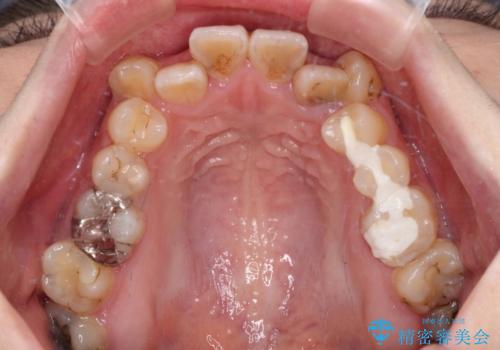

- 上下の歯が非接触であり、八重歯やむし歯を気にして来院された患者様です。

下顎骨の左右偏位はあるものの、上顎骨幅が相対的に狭い状態であったので、奥歯の咬み合わせが非常に乱れていました。

急速拡大装置により上顎骨幅を側方に拡大し、それを利用して八重歯を歯列に納めることにしました。

矯正治療後は全顎的にむし歯が多いため、セラミッククラウンやインレーにより補綴治療を行うこととしました。